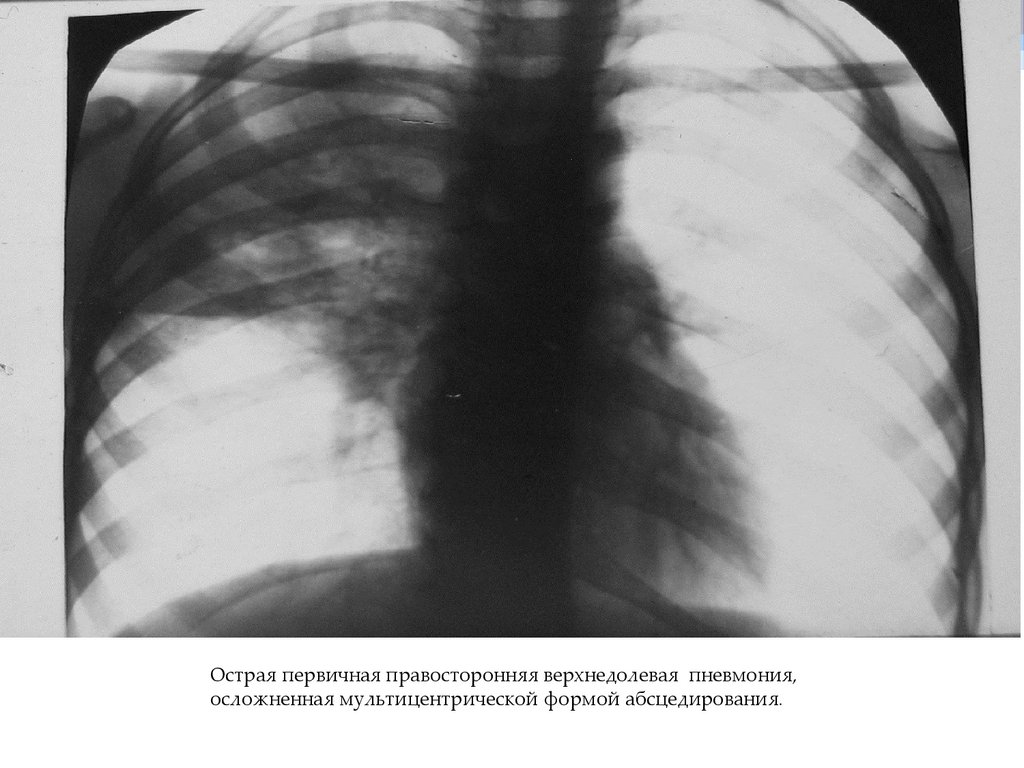

Острая первичная правосторонняя верхнедолевая пневмония,

осложненная мультицентрической формой абсцедирования.